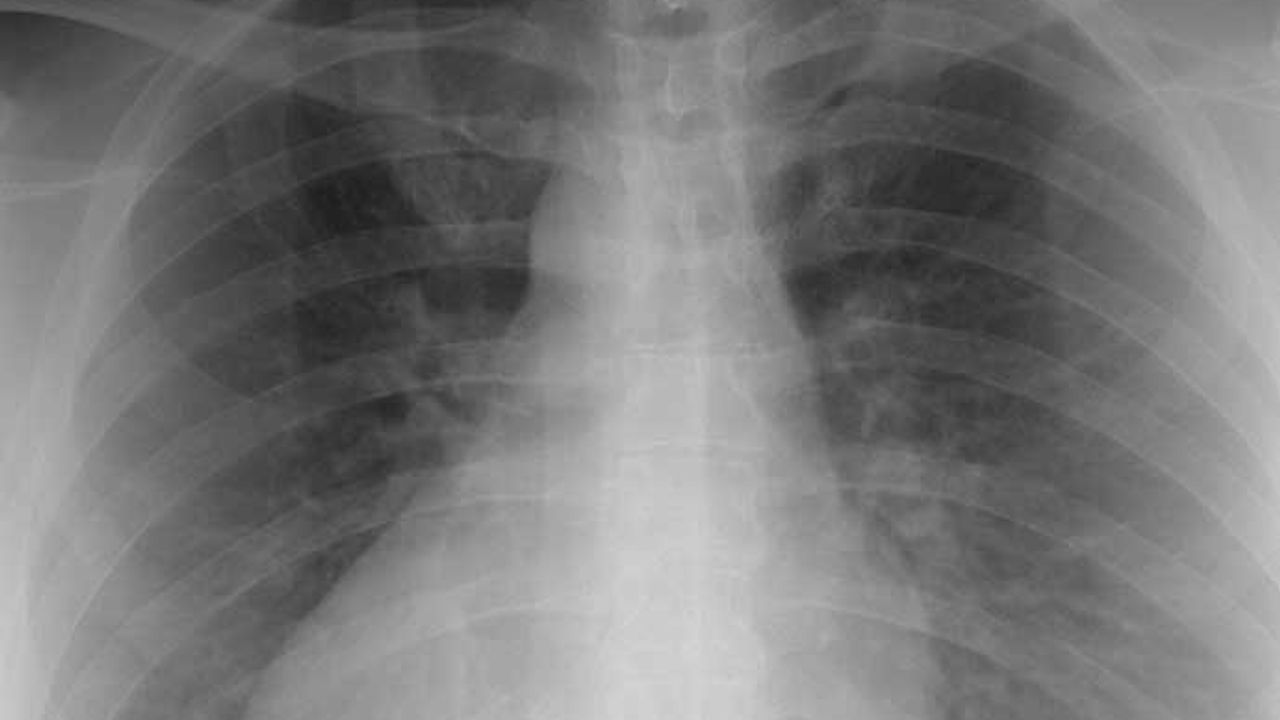

Mezotelyoma belirtileri genellikle ileri aşamalarda ortaya çıkar ve bu da hastalığı erken teşhis etmeyi zorlaştırır. Belirtiler arasında nefes darlığı, göğüs ağrısı, kilo kaybı ve iştah kaybı bulunabilir. Teşhis, fizik muayene, görüntüleme testleri (röntgen, bilgisayarlı tomografi) ve doku örneği analizi (biyopsi) yoluyla yapılır.